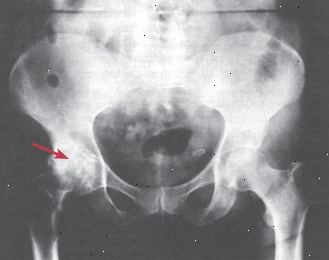

X-paprsky. Většina forem artritidy může způsobit kloubní abnormality vidět na rentgenových paprsků (viz obr. 4). Avšak ve většině případů, tyto změny nelze zjistit až měsíců po začátku onemocnění. Někdy jsou změny poměrně specifické a navrhnout konkrétní druh artritidy. V jiných případech, které jsou obecnější. Například, poškození kostí (tzv. eroze) se často vyskytuje u revmatoidní artritidy a může dojít ve dně, ale škody z každé příčiny se liší dost vzhledu, které radiolog obvykle řekněte jim od sebe.

Obrázek 4: artróza kyčelního kloubu Tato x-ray, nebo rentgenový snímek ukazuje osteoartrózy změny na levém boku. Normální tvar "ball-in-zásuvky" se znatelně zhoršila. |